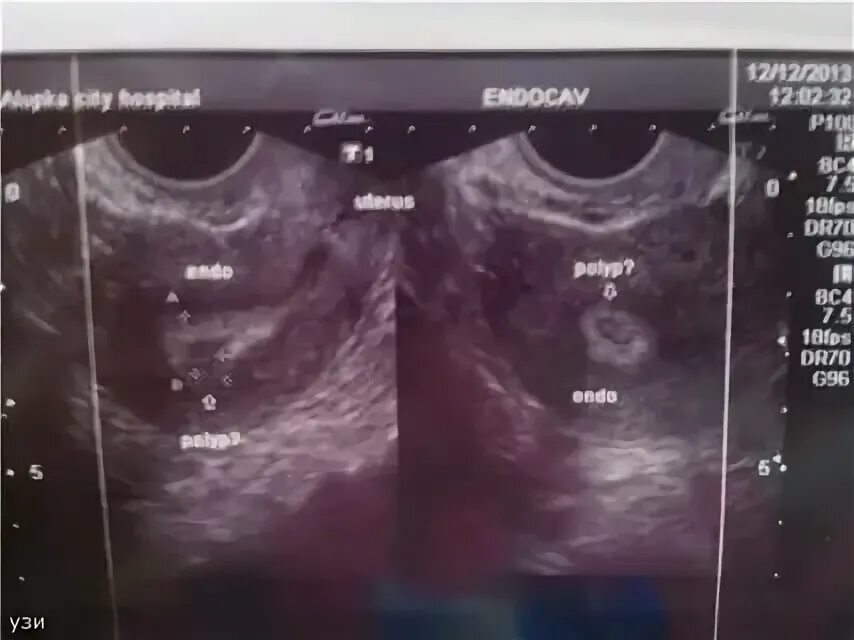

Когда можно идти на узи